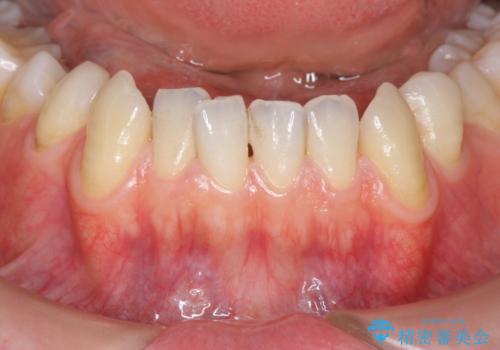

- 下の犬歯の歯茎の下がりを気にされていました。

矯正治療予定であったので、矯正治療前に歯茎の移植を行い、さらに退縮するのを防ぎました。

下がったのを元に戻すことは必ずしもできないですが、厚みを増やして下がりにくくすることはできます。今回左下の犬歯は特に、しっかり下がったのも元に戻すことができ、大変うまくいきました。